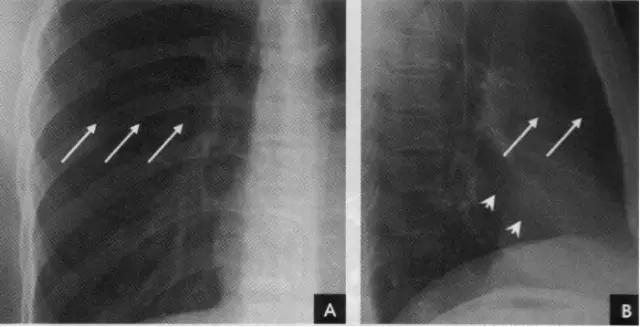

2、横裂又称水平裂,约70%的人正、撼位胸片均可显影。在正位片上表现为右中肺野横行细线状阴影,从第6肋腋部水平自外向内延伸.并止于肺门外lcm处。可向上或向下倾斜10:左右或略成曲线;在侧位片上,横裂起白斜裂中部,向前呈水平方向走行达前胸壁。其位置的改变可作为判断肺体积变化的标志(如上图)。 某些正常人可发生叶间裂不分、分裂不全或出现多余叶间裂等变异情况,因而叶间胸膜也发生相应的变化(参阅肺副叶)。